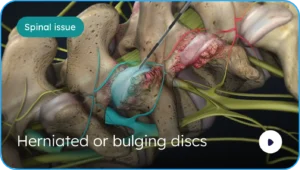

Precision Orthopaedic Surgery to Restore, Optimize, & Preserve.

Advanced orthopaedic care integrating surgical expertise, regenerative medicine, precision diagnostics, and longevity optimization under one roof.

A board-certified orthopaedic surgeon specializing in advanced surgical techniques

Physician-led, evidence-based care integrating regenerative medicine and precision-driven musculoskeletal optimization.

Precision Orthopaedics

Video Library Patient Education First

Comprehensive educational content covering orthopaedic surgery, regenerative medicine, peptide therapy, and evidence-based rehabilitation protocols.